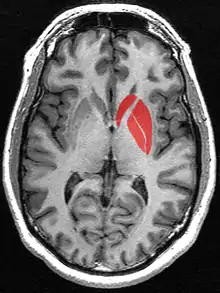

Striatum (in red) shown within the brain

(pink: amygdala; blue: thalamus)